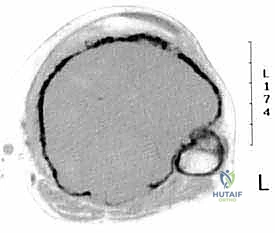

لفهم مدى تعقيد وعبقرية جراحة استئصال الظنبوب القريب، من الضروري الإبحار في أعماق التشريح الأساسي لهذه المنطقة الحيوية. لا يقتصر الأمر على مجرد عظام، بل هو نظام هندسي وبيولوجي متكامل ومعقد. يتكون مفصل الركبة من التقاء عظم الفخذ (Femur) من الأعلى، وعظم الساق أو الظنبوب (Tibia) من الأسفل، وعظم الشظية (Fibula) الجانبي، بالإضافة إلى الرضفة أو صابونة الركبة (Patella) في الأمام. الجزء القريب من الظنبوب هو الجزء العلوي العريض من عظم الساق، والذي يشكل القاعدة الأساسية التي يستند عليها مفصل الركبة ويتحمل وزن الجسم بأكمله.